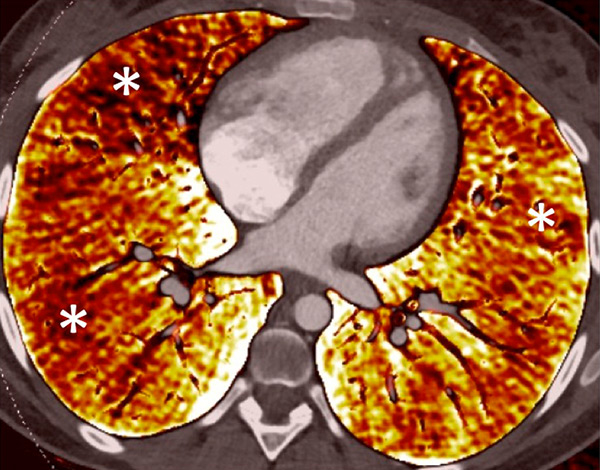

Perfusion could also be assessed with DECT in patients with PH caused by emphysema or lung fibrosis (fig. 11). The regional severity of pulmonary emphysema can be evaluated by correlating functional perfusion images with anatomical changes. Lee and coworkers found that DECT could be used for emphysema quantification and regional perfusion evaluation by use of iodine maps [45]. In emphysema, destruction of alveoli and interstitial spaces leads to a loss of pulmonary vessels, responsible for a decrease in perfusion. In lung fibrosis, perfusion defects reflect pathological processes such as small-vessel remodelling or fibrotic obliteration of the pulmonary vasculature.

Figure 11

Chronic obstructive pulmonary disease. Correlation between panlobular emphysema (A/B) and pulmonary hypoperfusion (C/D) (stars).